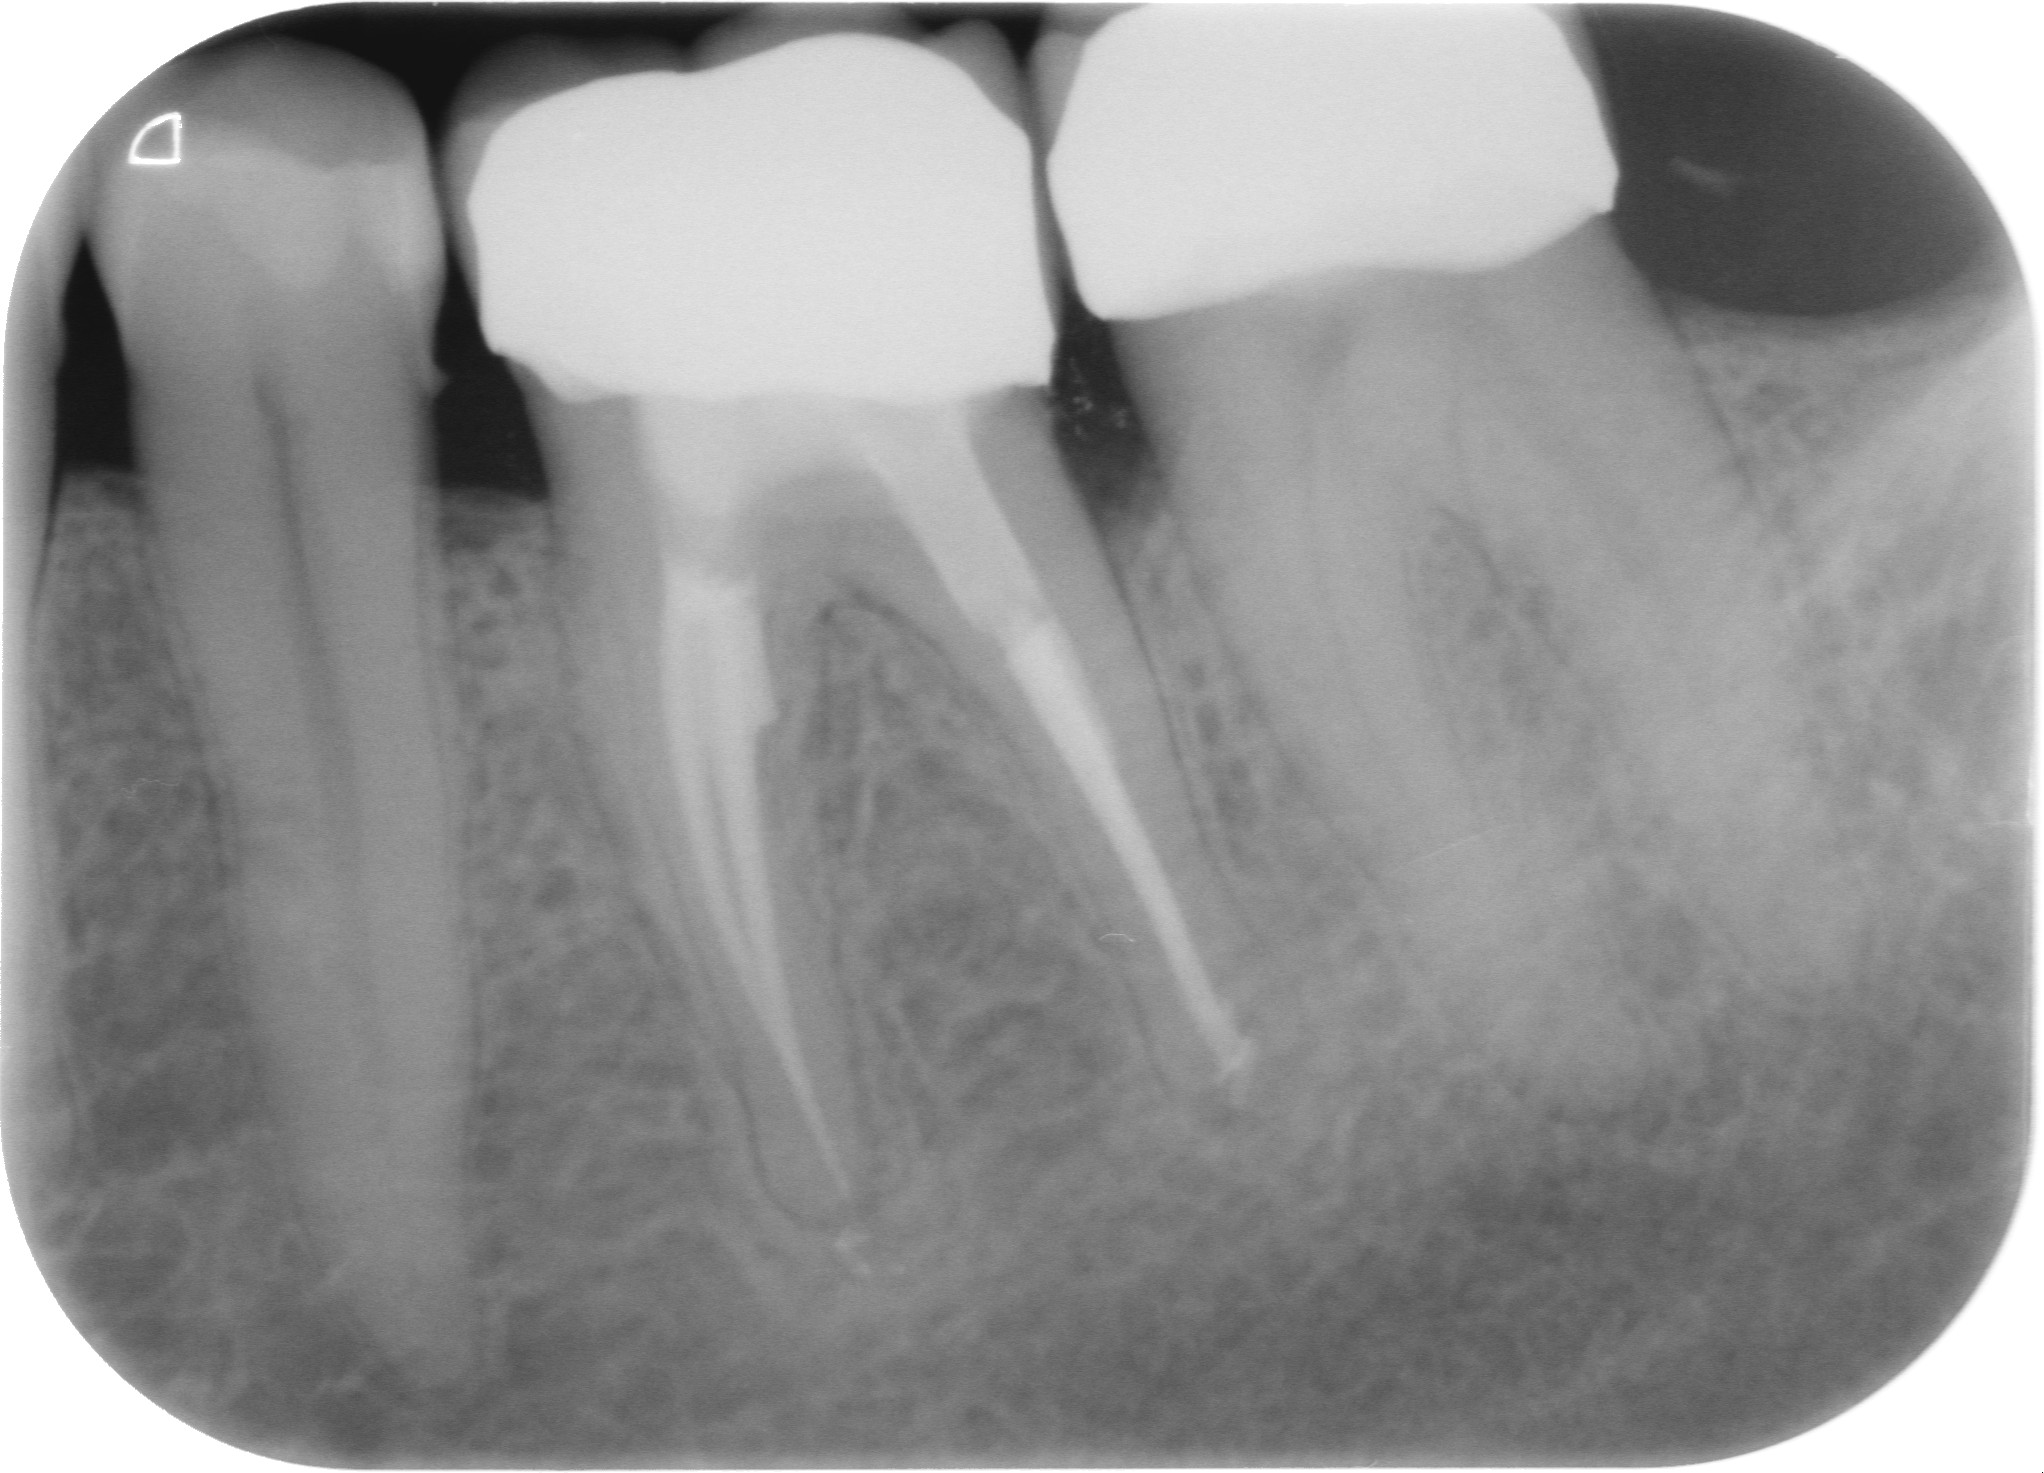

Fig. 3 : Contrôle radiographique après la finition de la prothèse.